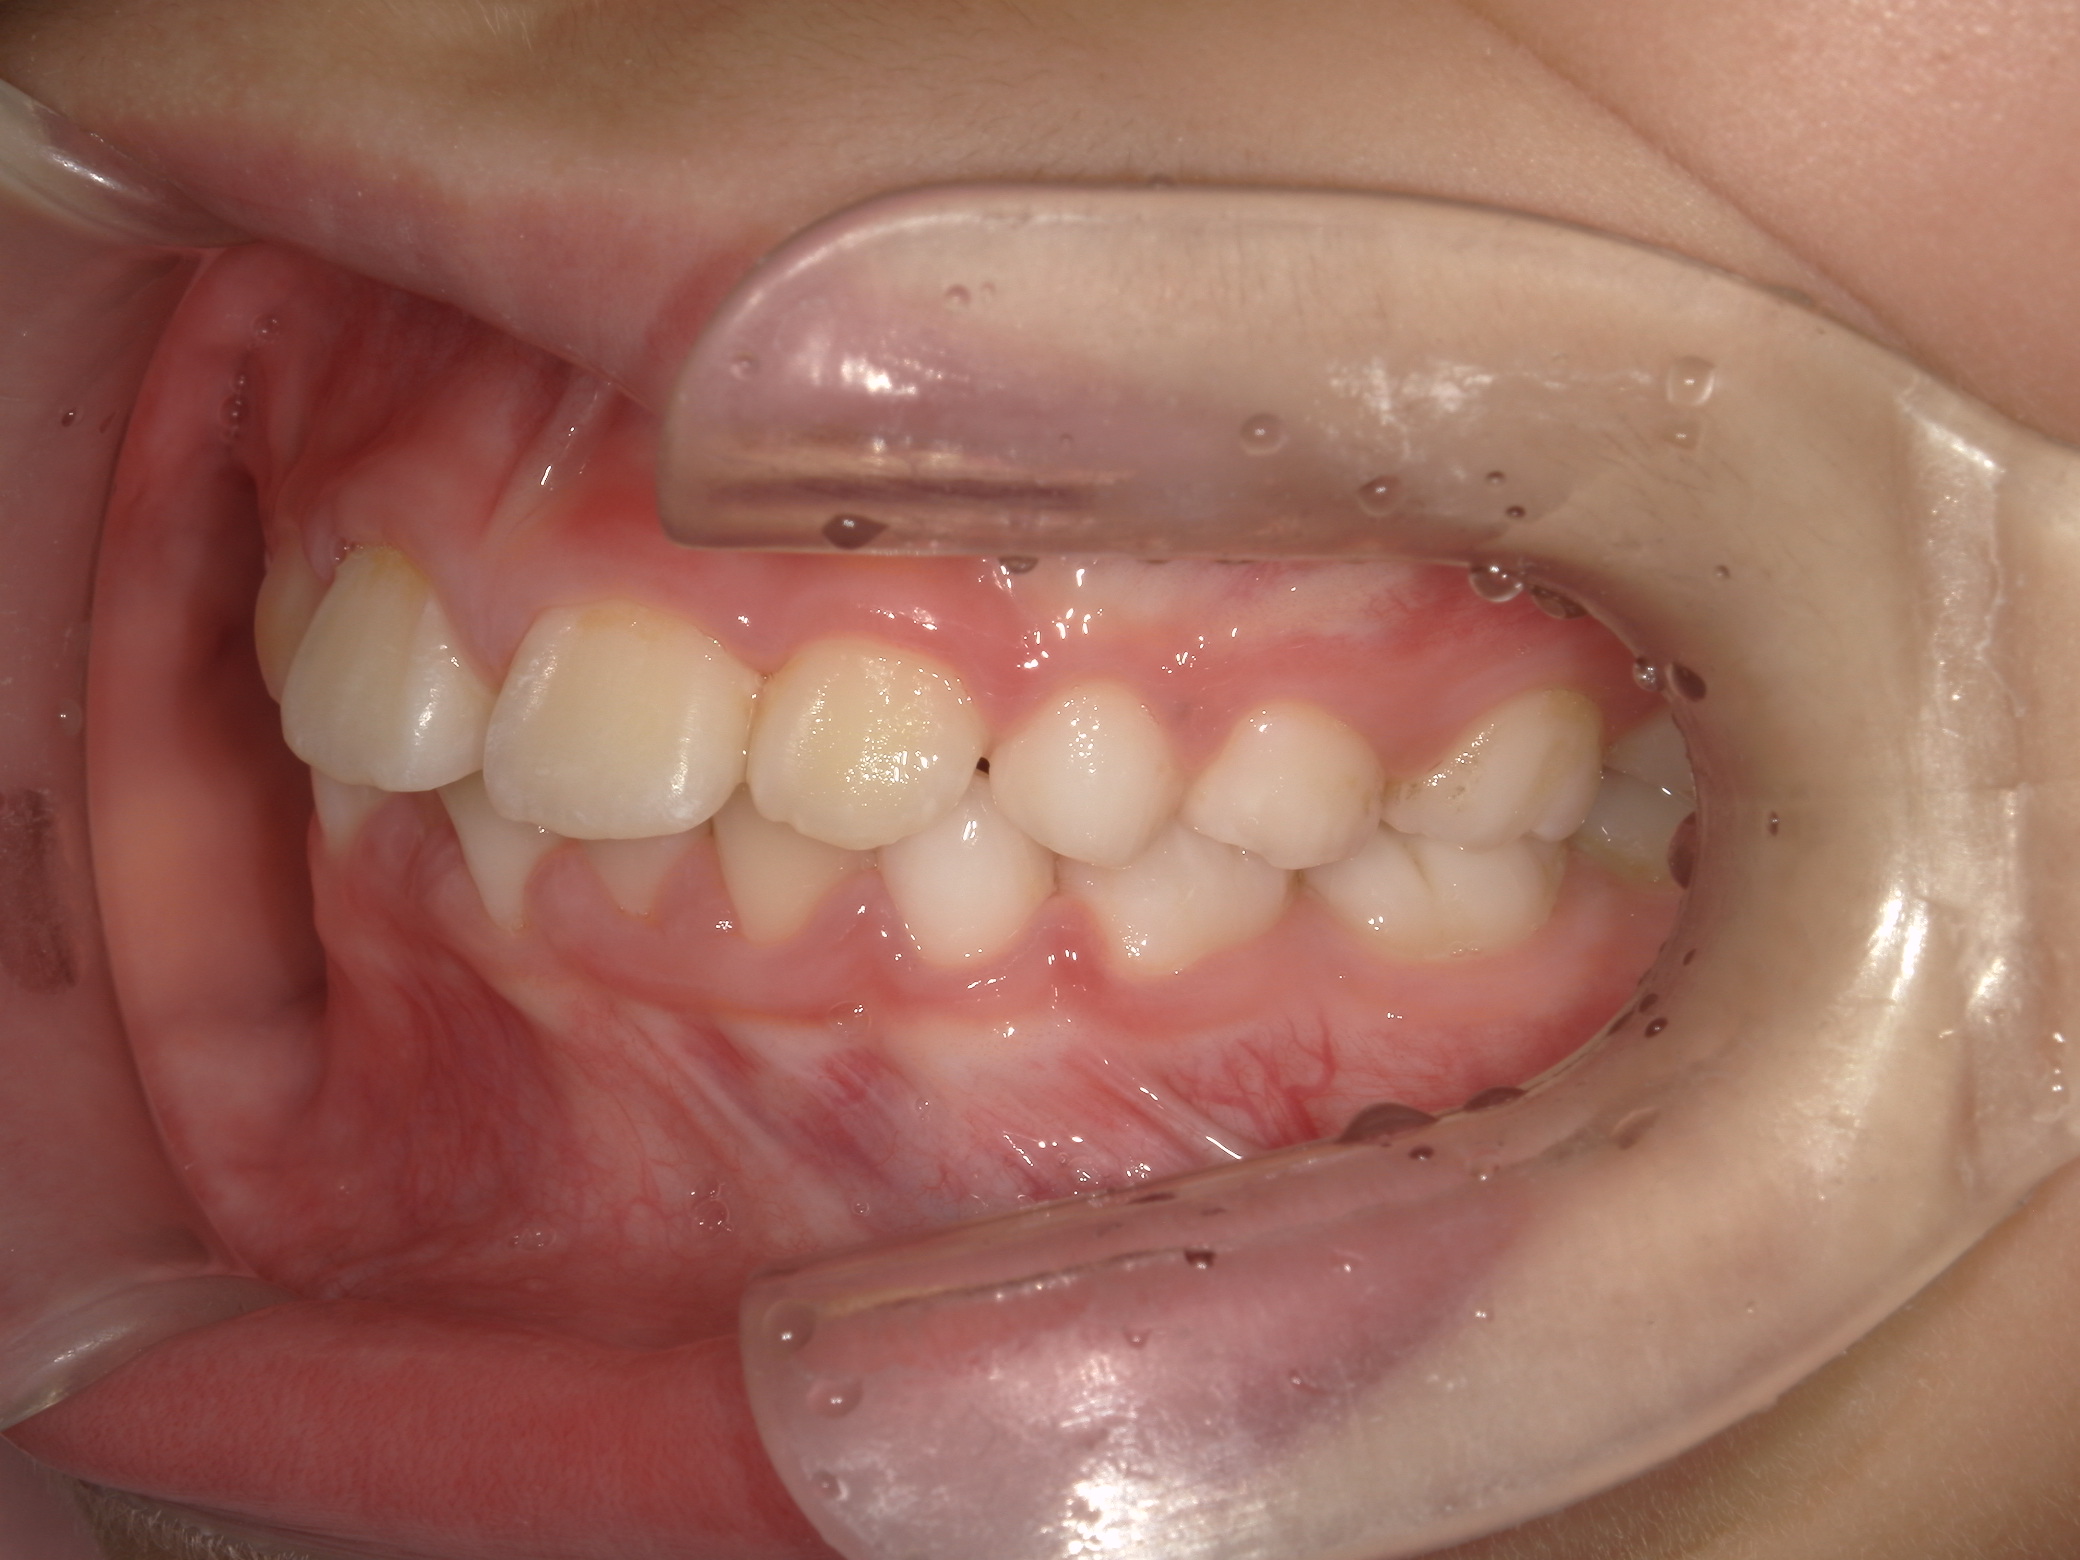

【小学生】 8歳 インビザライン矯正 過蓋咬合(深い咬み合わせ)と叢生(でこぼこ)を改善

小学生で開始

インビザライン ファースト

でこぼこ

非抜歯

1期治療のみで改善

Before

After

治療期間

1年4カ月年

治療開始

8歳

種類

インビザライン矯正

使用装置

インビザラインファースト(こどものインビザライン)

コメント

転勤族ということもあり、時間に制限がありましたが、患者さんがしっかり装置をつけてくれたので お引越しまでに終了することができました。

途中 側方の歯がどんどん生え変わって 最終的には全部永久歯で終了しました。

咬み合わせが深い場合、インビザラインファーストは咬み合わせを浅くするのに適しています。